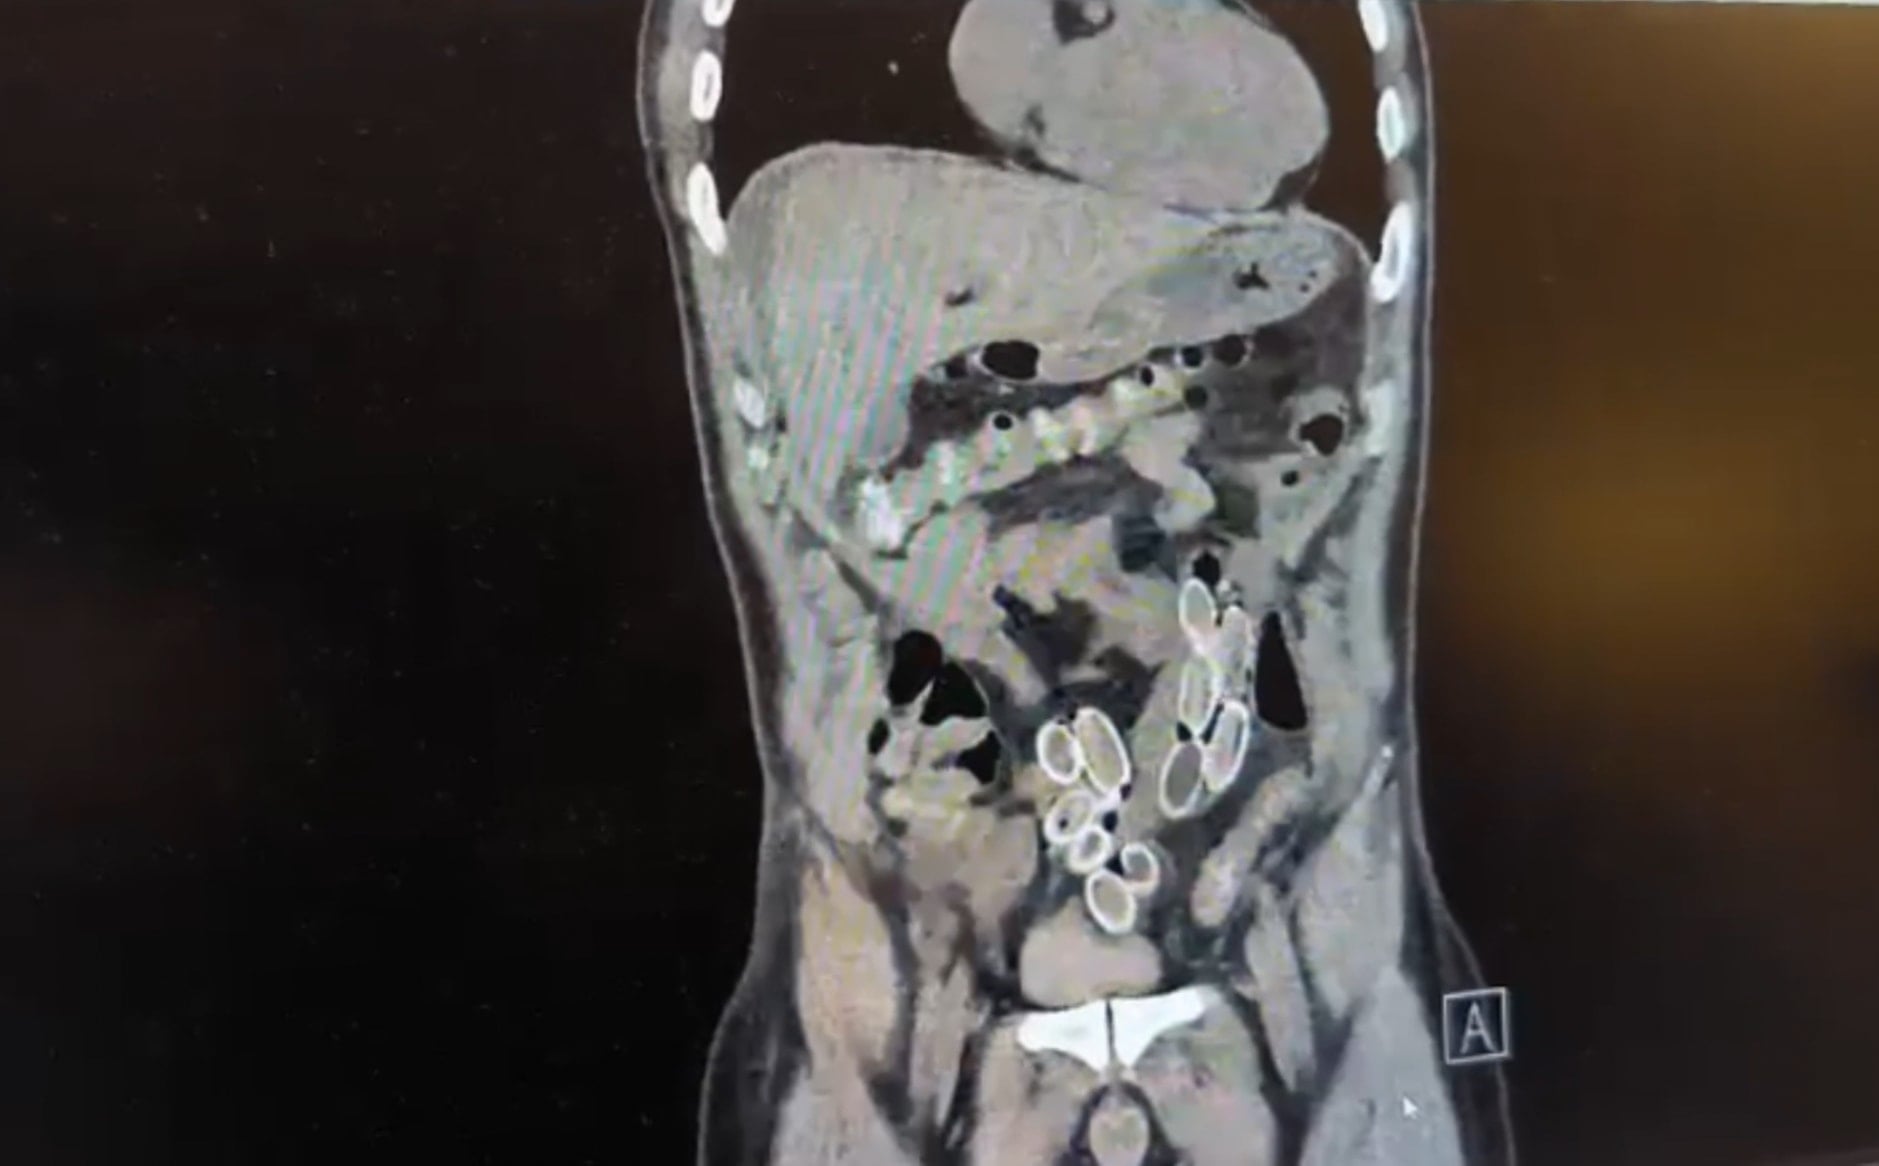

Yapılan muayenenin ardından çekilen tomografide Cüneyt Ç.’nin mide ve bağırsaklarında yabancı maddeler tespit edildi. Bunun üzerine hastane durumu polis ekiplerine bildirdi. İhbar sonrası Beşiktaş Asayiş Büro Amirliği ekipleri konuyla ilgili çalışma başlattı.

Doktorların değerlendirmesi sonrası ameliyata alınan Cüneyt Ç.’nin mide ve bağırsaklarından kapsül halinde toplam 49 adet esrar macunu çıkarıldı. Kapsüllerin toplam ağırlığının 259,7 gram olduğu öğrenildi. Şüpheliye ait bir cep telefonu da inceleme yapılmak üzere polis ekiplerine teslim edildi.